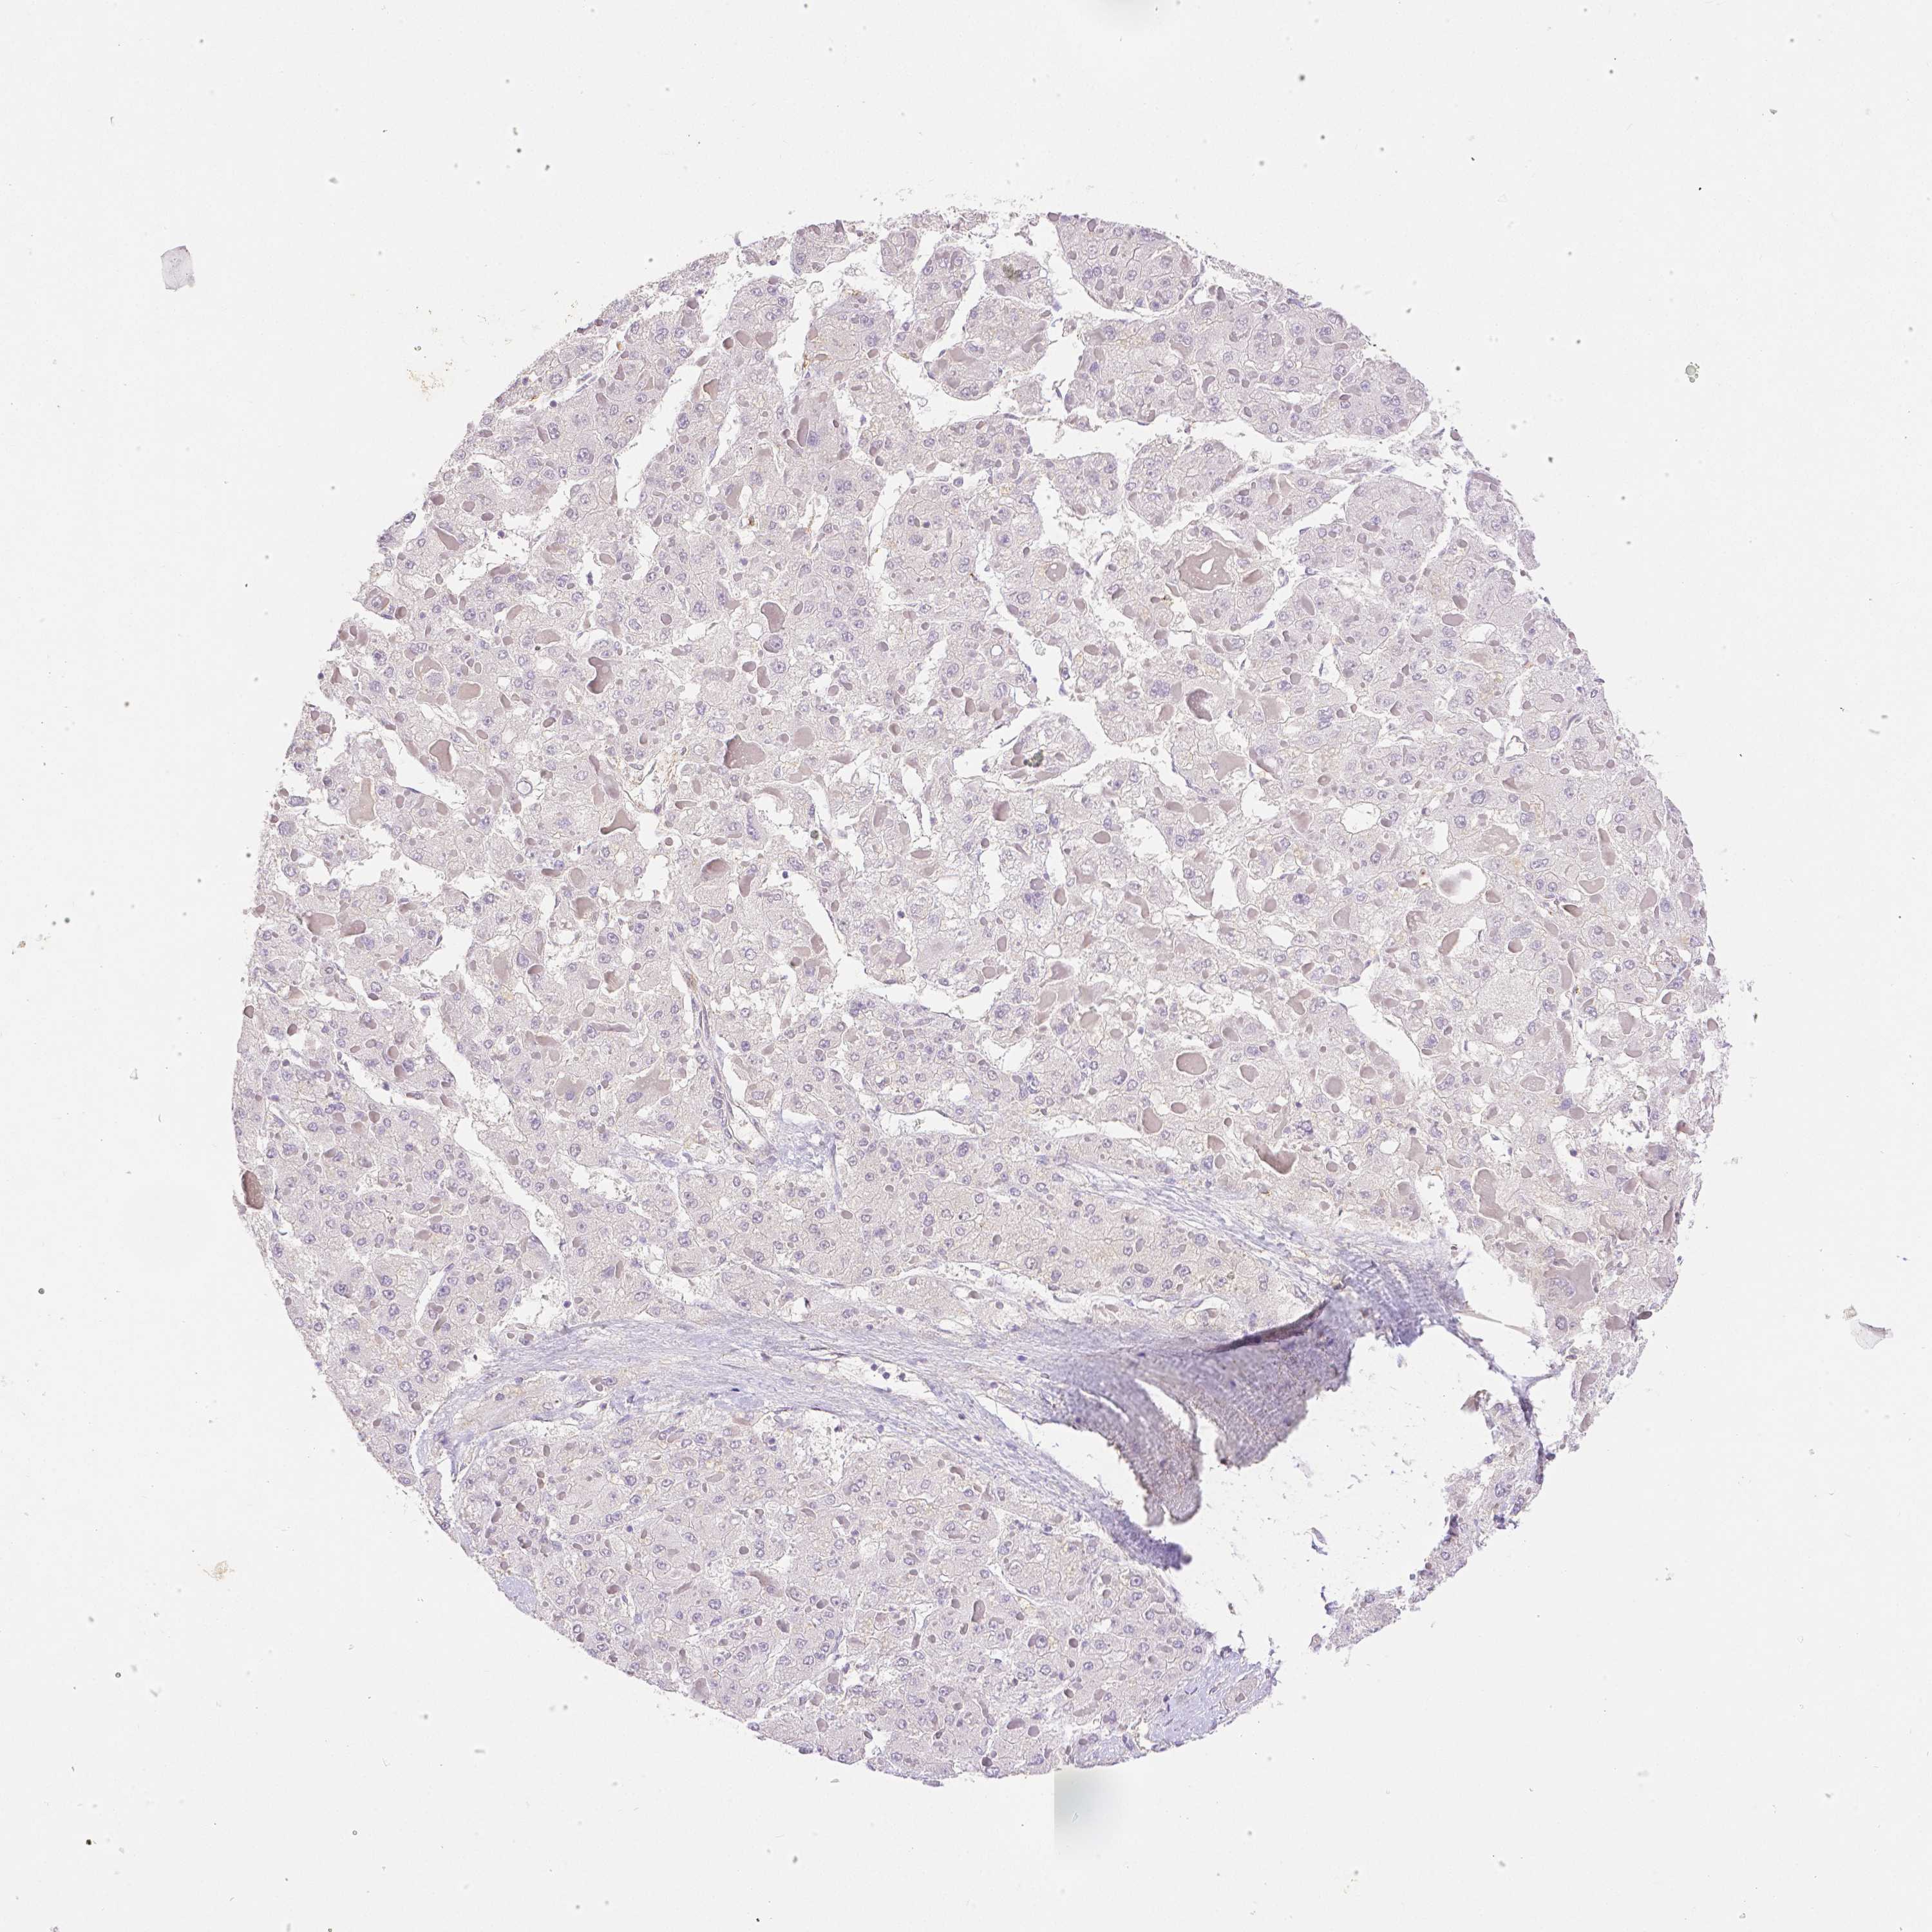

LIVER CANCER - Protein expressioni

A mouse-over function shows sample information and annotation data. Click on an image to view it in a full screen mode. Samples can be filtered based on level of antibody staining by selecting one or several of the following categories: high, medium, low and not detected. The assay and annotation is described here.

Note that samples used for immunohistochemistry by the Human Protein Atlas do not correspond to samples in the TCGA dataset.

Antibody stainingi

Antibody staining in the annotated cell types in the current human tissue is reported as not detected, low, medium, or high, based on conventional immunohistochemistry profiling in selected tissues. This score is based on the combination of the staining intensity and fraction of stained cells.

Each image is clickable and will lead to virtual microscopy that enables deeper exploration of all samples and also displays staining intensity scores, fraction scores and subcellular localization as well as patient and tissue information for each sample.

Antibody HPA003733

Antibody CAB068243

Antibody CAB068244

Carcinoma, Hepatocellular, NOS

Cholangiocarcinoma